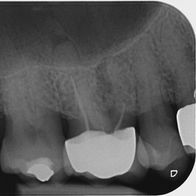

Orthograde Revisionsbehandlung

vorhandener Wurzelkanalfüllungen

vorher

nachher